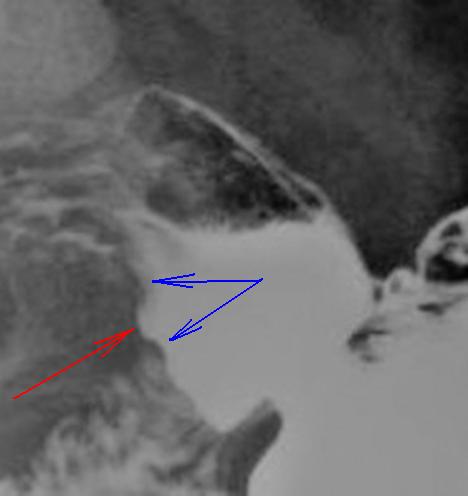

Я отвечу - "НЕТ", ибо данное скиалогическая картина, даже с учетом наличия "формальной ниши", мало похожа на "язву", и еще меньше на "язвенную болезнь желудка и 12-ти перстной кишки, с локализацией язвенной "ниши" в луковице 12-ти перстной кишки".

Данное мнение весьма субъективно, так как базируется только на "одном изображении", представленном в "прямой проекции"

На "обзорном снимке" нашли отображение два главных скиалогических симптома "язвы" - "контур ниша" и симметричный воспалительный "вал". Конечно, если бы, имела место еще и "конвергенция складок" слизистой к "нише", то высказать что-то, было-бы проблемно. Смущает и сама ниша "соскообразная" (а не коническая) и мысли, конечно в сторону "хронической", но тогда "вал"?, отсутствие "деформации" луковицы при "такой нише"?, отсутствие "перипроцесса"?

1. Уменьшение луковицы 12-ти перстной кишки в размерах, с выраженной её деформацией. Можно, кстати, вспомнить и закономерность Варфаламея Артемьевича Фанарджяна. Весьма полезная закономерность.

2. "Рельеф - ниша" с выраженной конвергенцией складок слизистой к "нише". Резкий отек и деформация складое слизистой луковицы 12-ти перстной кишки.

3. "Рельеф- ниша", с выраженной конвергенцией отечных складок слизистой к "нише", деформация складок.

4. "Контур - ниша". Хорошо видна также конвергенция складок слизистой к "нише".

Рентгенологически язва по задней стенке. Продолжение "этого случая" еще последует. Пусть это не прозвучит высокомерно, но мы вынуждены, не ориентироваться на "наших" эндоскопистов. Наши эндоскописты даже не берут материала для гистологии, везде свои заморочки. Я считаю, что лечащий врач, коллега клиницист, получив данные от врачей исследователей, сделает правильный вывод, и за этим последует "клинический синтез".

А как вам тут луковица? есть признаки рубцовой деформации? На мой взгляд есть.

Признаки есть, но и только. Слишком много «чёрного»).